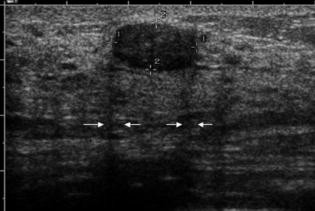

Fibroadenom Sonographisch typisches Fibroadenom mit länglichovaler, gelappter Form bei insgesamt glatter Berandung Das Fibroadenom ist ein gutartiger Tumor der Brust und bedarf in dieser typischen Ausprägung keiner Biopsie, sollte aber über einen kurzen Zeitraum kontrolliert werden. Gutartige Brusttumoren sind Geschwulste der weiblichen Brust, die – je nach Tumorgröße und art – auch verschiedene Symptome hervorrufen können Fibroadenome machen meist keine Beschwerden, da sie in der Regel nicht schmerzhaft sind Die betroffenen Frauen erstasten die harten Knoten meist zufällig oder bei der Selbstuntersuchung der BrustBei sehr schlanken Frauen und wenn der Tumor. Das Fibroadenom meldet sich als „Klassiker“ unter den gutartigen Tumoren der Frau vor der Menopause zumeist sind jüngere Frauen unter 40 Jahren betroffen, mit einem Altersgipfel von ca 25 Jahren Der Tumor ist ein gutartiger Mischtumor, der von der Frau meistens ertastet werden kann.

Ein gutartiger Tumor in der Brust ist eine harmlose Gewebsveränderung und entwickelt sich nur äußerst selten zu einem bösartigen Tumor Nur jedes tausendste Fibroadenom entwickelt sich zu Brustkrebs Trotzdem sollte bei einem gutartigen Tumor die Brust regelmäßig von einem Arzt untersucht werden. Fibroadenom Sonographisch typisches Fibroadenom mit länglichovaler, gelappter Form bei insgesamt glatter Berandung Das Fibroadenom ist ein gutartiger Tumor der Brust und bedarf in dieser typischen Ausprägung keiner Biopsie, sollte aber über einen kurzen Zeitraum kontrolliert werden. Aus diesem Grund wurde angenommen, dass sie das zukünftige Risiko eines bösartigen Tumors nicht erhöhten Die Wissenschafter untersuchten Biopsieproben von 9087 Frauen zwischen 18 und 85 Jahren mit gutartigen Knoten in der Brust, die zwischen 1967 und 1991 in der Klinik behandelt worden waren.

Wird ein gutartiger Tumor (zB ein Fibroadenom) diagnostiziert, so gibt es die Möglichkeit, dieses minimalinvasiv mittels Vakuumbiopsien zu entfernen Bis zu einer Grösse von zwei Zentimetern können diese Knoten unter Ultraschallkontrolle in lokaler Betäubung mit einer Biopsie Nadel entfernt werden. Jedenfalls Tut es ab und zu weh und heute habe ich die ganze. Der häufigste gutartige Tumor in der Brust ist das Fibroadenom Wird ein gutartiger Tumor in der Brust entdeckt, erfolgt die weitere Diagnose meist mittels Sonographie oder auch Das Abtasten der Brust gehört zur Standardkontrolle bei jedem Frauenarztbesuch Auch zu Hause sollte die Brust regelmäßig selbst auf Knoten untersucht werden.